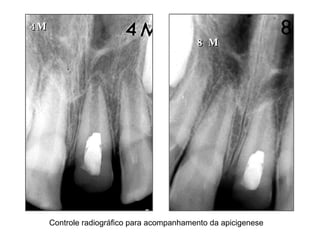

4M 8 M Controle radiográfico para acompanhamento da apicigenese

4M 8 MControle radiográfico para acompanhamento da apicigenese